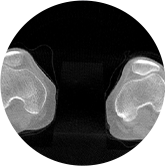

膝關節

關閉金屬偽影校正

開啟金屬偽影校正